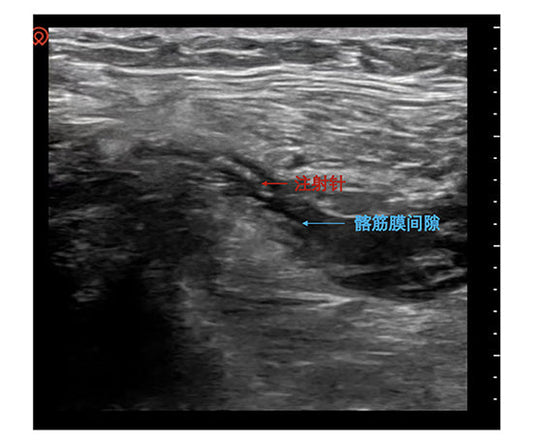

The expert team at Fuwai Hospital (Beijing) has successfully pioneered Renal Denervation (RDN) for Refractory Hypertension (RH). By utilizing radiofrequency energy to suppress hyperactive sympathetic drive, this procedure offers a...